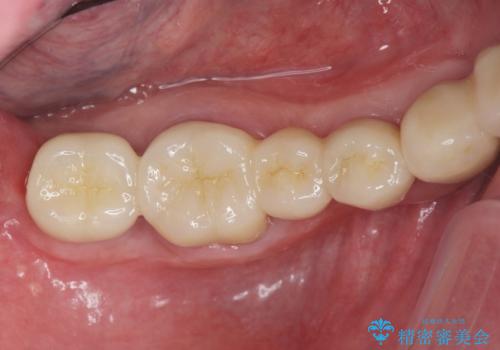

重度に吸収してしまった歯槽骨をしっかりと造成を行ったのちにインプラント治療を行ったので、安定した歯周環境にすることができました。